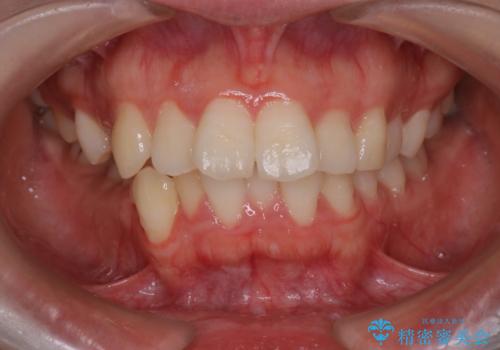

【抜歯インビザ】凸凹を綺麗になおしたい

- 前歯の凸凹を主訴に来院されました。

叢生量が多いため、抜歯が必要となるため、ワイヤー矯正をお勧めしましたが、患者さんの希望によりインビザラインで治療を開始しました。途中でワイヤーリカバリーを必要とせず終了でき患者さんには満足していただけました。